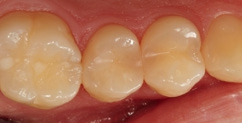

Fall 6 Minimalinvasive Behandlung von tiefen Approximalläsionen an Zähnen 14 und 15

Bei dem 26-jährigen, frisch approbierten Zahnarzt imponierte eine untypisch hohe Kariesaktivität mit etlichen, teils sehr tiefen Approximalläsionen, die einer therapeutisch- restaurativen Intervention bedurften. An den Zähnen 14 und 15 zeigte sich eine auffällige Transluzenzänderung des Zahnschmelzes, was immer ein untrügerisches Zeichen für eine darunterliegende, bereits in das Dentin penetrierte Karies darstellt (Abb. 23). Die Abbildung 24 verdeutlicht – noch während der Exkavation – das Ausmaß des vorgefundenen Defektes. In der Abbildung 25 sind die vollständigen Kavitäten, bereits mit Teilmatrizen und einem Palodent V3-Spannring isoliert, erkennbar. Durch den hervorragenden Separationsdruck dieser Art von Spannringen können benachbarte Approximalläsionen in der Regel problemlos zeitgleich versorgt Anwerden. Nach der adhäsiven Vorbehandlung – im vorliegenden Fall mit einem klassischen Mehrflaschen-Etch&Rinse- Adhäsiv (Abb. 26) – erfolgte die Versorgung mit SDR flow+ in der Farbe A3 in zwei horizontalen Inkrementen. Beide Inkremente, die eine Dicke von ca. 3 mm aufwiesen, wurden für je 40 Sekunden gemäß Herstellerangaben polymerisiert. Eine gemeinsame abschließende Polymerisation für 20 Sekunden nach Entfernen der Matrizen ergänzte das Aushärtungsprotokoll. Die Abbildung 27 zeigt die Situation direkt nach Ausarbeitung und Politur, die Abbildung 28 bei einer weiteren Nachkontrolle nach drei Monaten. Es zeigte sich nach der Rehydrierung der Strukturen eine deutlich bessere Farbadaptation als initial, unmittelbar nach dem Legen.